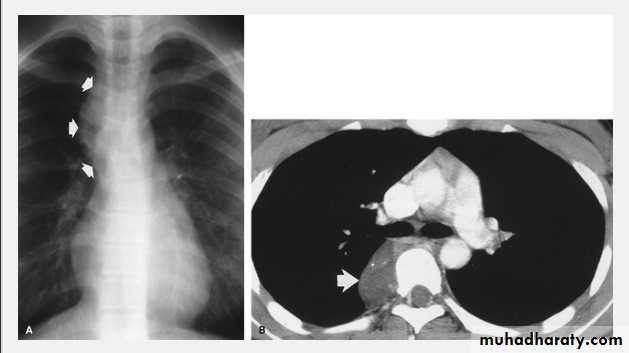

Tension pneumothorax.

On a posteroanterior chest x-ray (A), the left hemithorax is very dark or lucent because the left lung has collapsed completely (white arrows).

The tension pneumothorax can be identified because the mediastinal contents, including the heart, are shifted toward the right, and the left hemidiaphragm is flattened and depressed. A computed tomography scan done on a different patient with a tension pneumothorax (B) shows a completely collapsed right lung (arrows) and shift of the mediastinal contents to the left.

chest practice

Tension Pneumothorax. Portable chest film in a 43-year-old woman with ARDS shows a large right pneumothorax with mediastinal shift and ipsilateral diaphragmatic depression, suggesting tension.

Air was evacuated under pressure during emergent placement of a right chest tube.